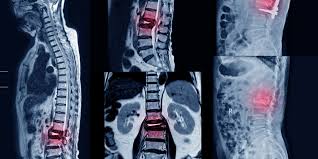

Señales de alerta para descartar fracturas vertebrales en pacientes con dolor lumbar

La evidencia disponible no apoya el uso de muchas señales de alerta para descartar específicamente fracturas vertebrales en pacientes con dolor lumbar (DL). Sobre la base de la evidencia de estudios individuales, pocas señales de alerta individuales parecen informativas debido a que la mayoría tienen una exactitud diagnóstica deficiente según lo indican los cálculos imprecisos de los cocientes de probabilidad. Cuando se usaron combinaciones de señales de alerta el rendimiento pareció mejorar. Cochrane Database Syst Rev. 28 de noviembre de 2023